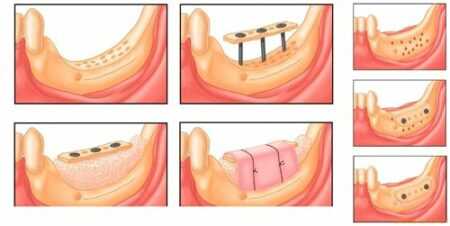

- Технология Split-Control. Основное назначение данной процедуры - расширение челюстной кости для возможности последующего проведения имплантации. Процедуру выполняют следующим образом. Специалист распиливает гребень, в полость размещает биоматериал, заменитель костной ткани, производит наложение швов.

- Межкортикальная остеомия. Подразумевает под собой расщепление альвеолярного отростка с целью коррекции костной структуры. В ходе хирургического вмешательства производится пропил гребня для формирования подвижного фрагмента, который затем стоматолог-хирург перемещает в другую часть, где наблюдается недостаток костной ткани. Подвижная часть фиксируется при помощи специальных винтов, полость заполняется биоматериалом.

Костную ткань можно нарастить

Поэтому в современной стоматологии полость, оставшуюся после удаления зуба, обычно заполняют специальным материалом, что позволяет сохранить костную ткань и в будущем установить имплантаты. Даже если протезирование не планируется, сохранить альвеолярный отросток все равно важно, ведь его целостность влияет на состояние всей челюсти. Например, удаление зубов мудрости тоже должно заканчиваться заполнением пустот костозамещающим материалом, чтобы сохранить соседние зубы.

При значительной атрофии кости стоматологи-хирурги выполняют операцию по наращиванию костной массы. При этом могут использоваться собственная костная ткань пациента или искусственные материалы (например, разновидность кальция фосфата).